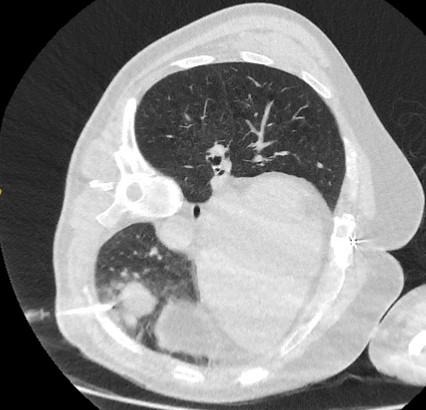

PET-CT com 18-fluordesoxiglucose (18-FDG) mostrando baixa captação em lesão semissólida posterior no lobo superior direito. A ressecção cirúrgica confirmou adenocarcinoma com padrão primariamente lepídico

Do acervo de Dr. George Tsaknis, MD, PhD, FRCP (Londres), MRQA, MAcadMEd, PGCert; usado com permissão